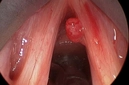

Faranjit, boğazın arka kısmında iltihaplanma ile ortaya çıkan bir rahatsızlıktır. Virüsler, bakteriler veya alerjenlerden kaynaklanabilir. Belirtileri arasında boğaz ağrısı ve yutkunma zorluğu bulunur. Tedavi yöntemleri arasında sıvı alımını artırmak, tuzlu su ile gargara yapmak ve dinlenme yer alır. Bu içerik, faranjit ile başa çıkma yollarını detaylandırmaktadır.

Faranjit, genellikle boğazın arka kısmında meydana gelen iltihaplanma ile karakterize edilen bir durumdur. Bu durum, virüsler, bakteriler veya alerjenler gibi çeşitli etkenlerden kaynaklanabilir. Faranjit, genellikle boğaz ağrısı, yutkunma zorluğu ve bazen ateş gibi belirtilerle kendini gösterir. Faranjiti tedavi etmek ve semptomları hafifletmek için çeşitli yöntemler bulunmaktadır. Bu yazıda, faranjite neyin iyi geleceği üzerine detaylı bir inceleme yapılacaktır. 1. Sıvı Tüketiminin ArtırılmasıFaranjit sırasında boğazın nemli kalması, iltihaplanmayı azaltabilir. Bu nedenle, bol miktarda sıvı tüketmek önemlidir.